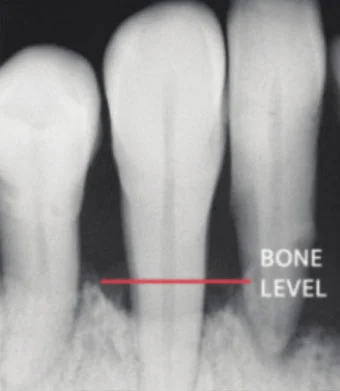

Dental x-rays can check for the amount of bone supporting your teeth. If low bone levels are spotted, it could be a sign of damage from gum disease.

Healthy gums have bone that supports the teeth.

Gum disease can create bone loss.